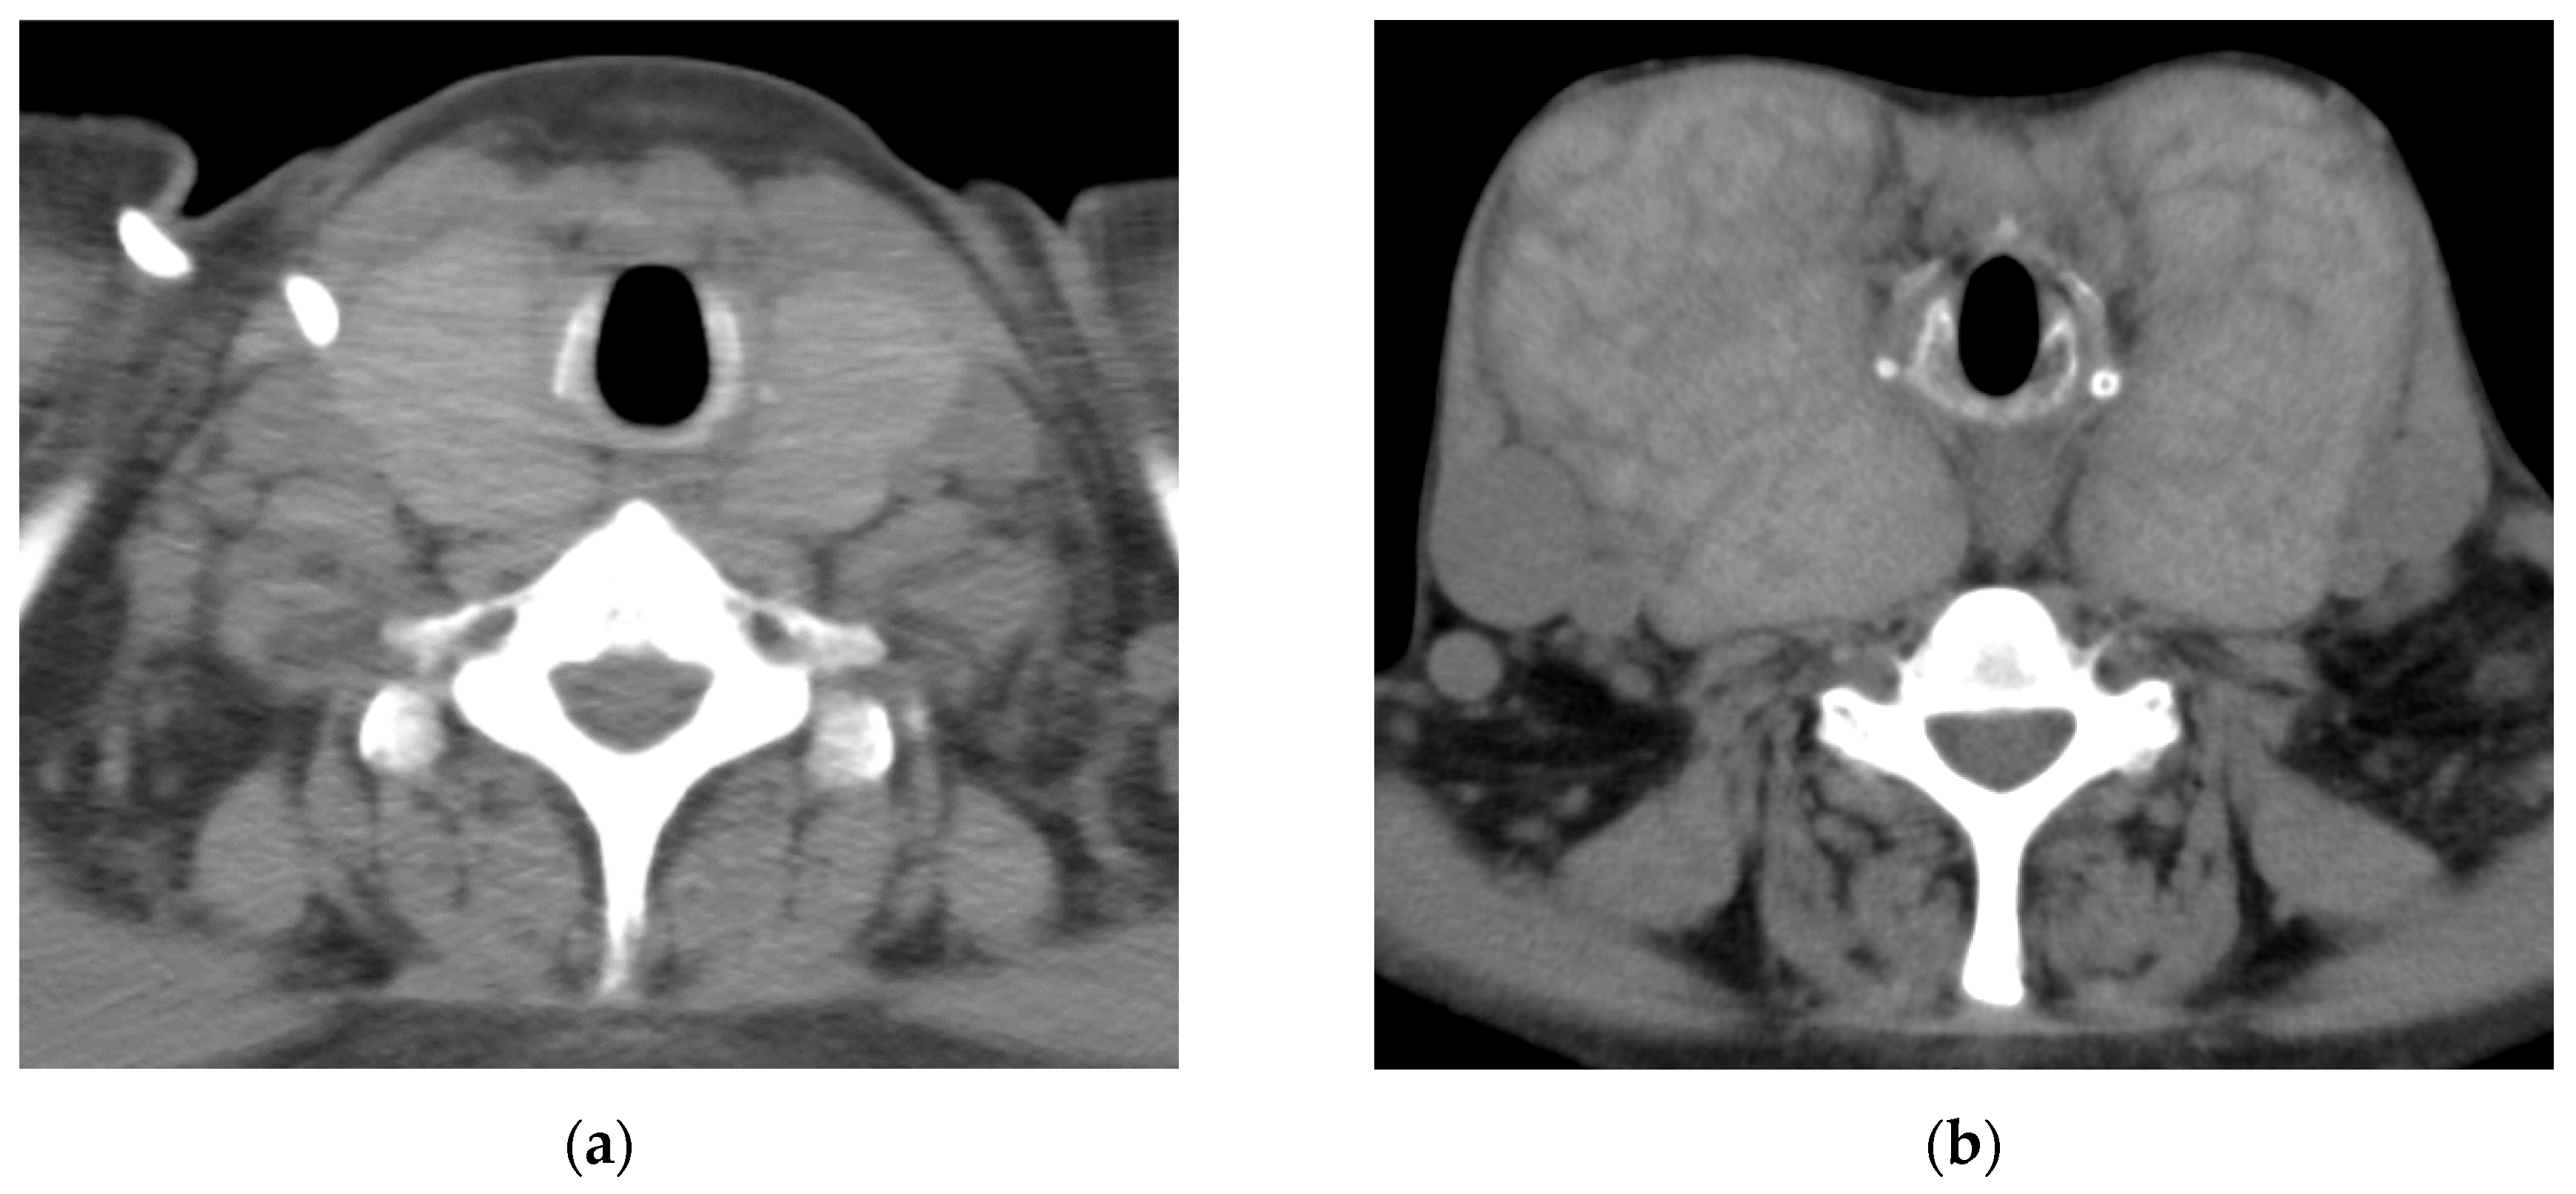

A 34-year-old woman was diagnosed with primary pulmonary hypertension (PPH). At that time, the current IPAH was called PPH. Then she underwent right heart catheterization, and her mean pulmonary artery pressure was 73 mmHg. She complained of dyspnea at rest corresponding to World Health Organization functional class IV. After diagnosing with PPH, she was treated with continuous intravenous epoprostenol. At 37 years of age, she started complaining of neck swelling. Thyroid studies showed Thyroid-stimulating hormone (TSH) = 0.01 μIU/mL (normal range: 0.35-4.94 μIU/mL), Free T3 = 19.88 pg/mL (normal range: 1.71-3.71 pg/mL), Free T4 = 4.86 pg/mL (normal range: 0.70-1.48 pg/mL), thyroid stimulating antibody = 465% (normal range: 0-180%), so she was diagnosed with Grave’s disease and prescribed thiamazole. Epoprostenol at this time was 15 ng/kg/min. Epoprostenol was titrated to decrease mean pulmonary artery pressure in combination with an endothelin receptor antagonist and a phosphodiesterase 5 inhibitor [10]. Epoprostenol maintained at 60-70 ng/kg/min after 14 years of treatment, and mean pulmonary artery pressure decreased to 30-35 mmHg. Thyroid function was controlled by therapy for Grave’s disease using thiamazole and levothyroxine. Nevertheless, her thyroid gland enlargement worsened as epoprostenol was titrated (Figure 1a, b). At 56 years of age, she was admitted to the local hospital due to worsening dyspnea. However, cardiogenic shock and respiratory failure with hypercarbonemia were observed, and she was transferred to our hospital the next day. At admission to our hospital, the patient’s vital signs were blood pressure of 97/62 mmHg, pulse of 117 bpm, and oxygen saturation of 88% with oxygen at 10 L/min through the mask. On examination, the auscultation revealed coarse crackles in her lungs and strider in her neck. Radiography of the chest revealed bilateral pulmonary congestion and airway stenosis (Figure 2a). Computed tomography of the chest also revealed airway stenosis by her giant goiter (Figure 2b). Blood gas analysis on 10 L/min of oxygen showed pH: 7.2, PaO2: 63.7 mmHg, PaCO2: 73.9 mmHg and HCO3-: 28.4 mmol/L, indicating respiratory failure with hypercarbonemia. Thyroid studies showed TSH = 2.265 μIU/mL, Free T3 = 1.52 pg/mL, Free T4 = 0.90 pg/mL. Tracheal intubation was difficult due to severe airway stenosis. Treatment with noninvasive positive pressure ventilation, dobutamine, and noradrenaline was ineffective, and she passed away on the 12th day after admission. Pathological autopsy was performed. Gross thyroid findings included diffuse enlargement (weight 675 g, size 14 cm x 6 cm) and compressive constriction of the upper airway by the thyroid gland (Figure 3). Histological findings of the thyroid gland showed increased thyroid follicle growth and increased colloidal resorption, suggesting a hyperthyroid state (Figure 4). There were no obvious malignant findings. The cause of death was considered to be respiratory failure due to airway narrowing caused by thyroid gland enlargement. The enlarged goiter was thought to be due to continuous intravenous epoprostenol therapy for IPAH.

Figure 1. Computed tomography imaging course of thyroid gland enlargement. The thyroid gland markedly increased. (a)At 45 years of age; (b)At 54 years of age.